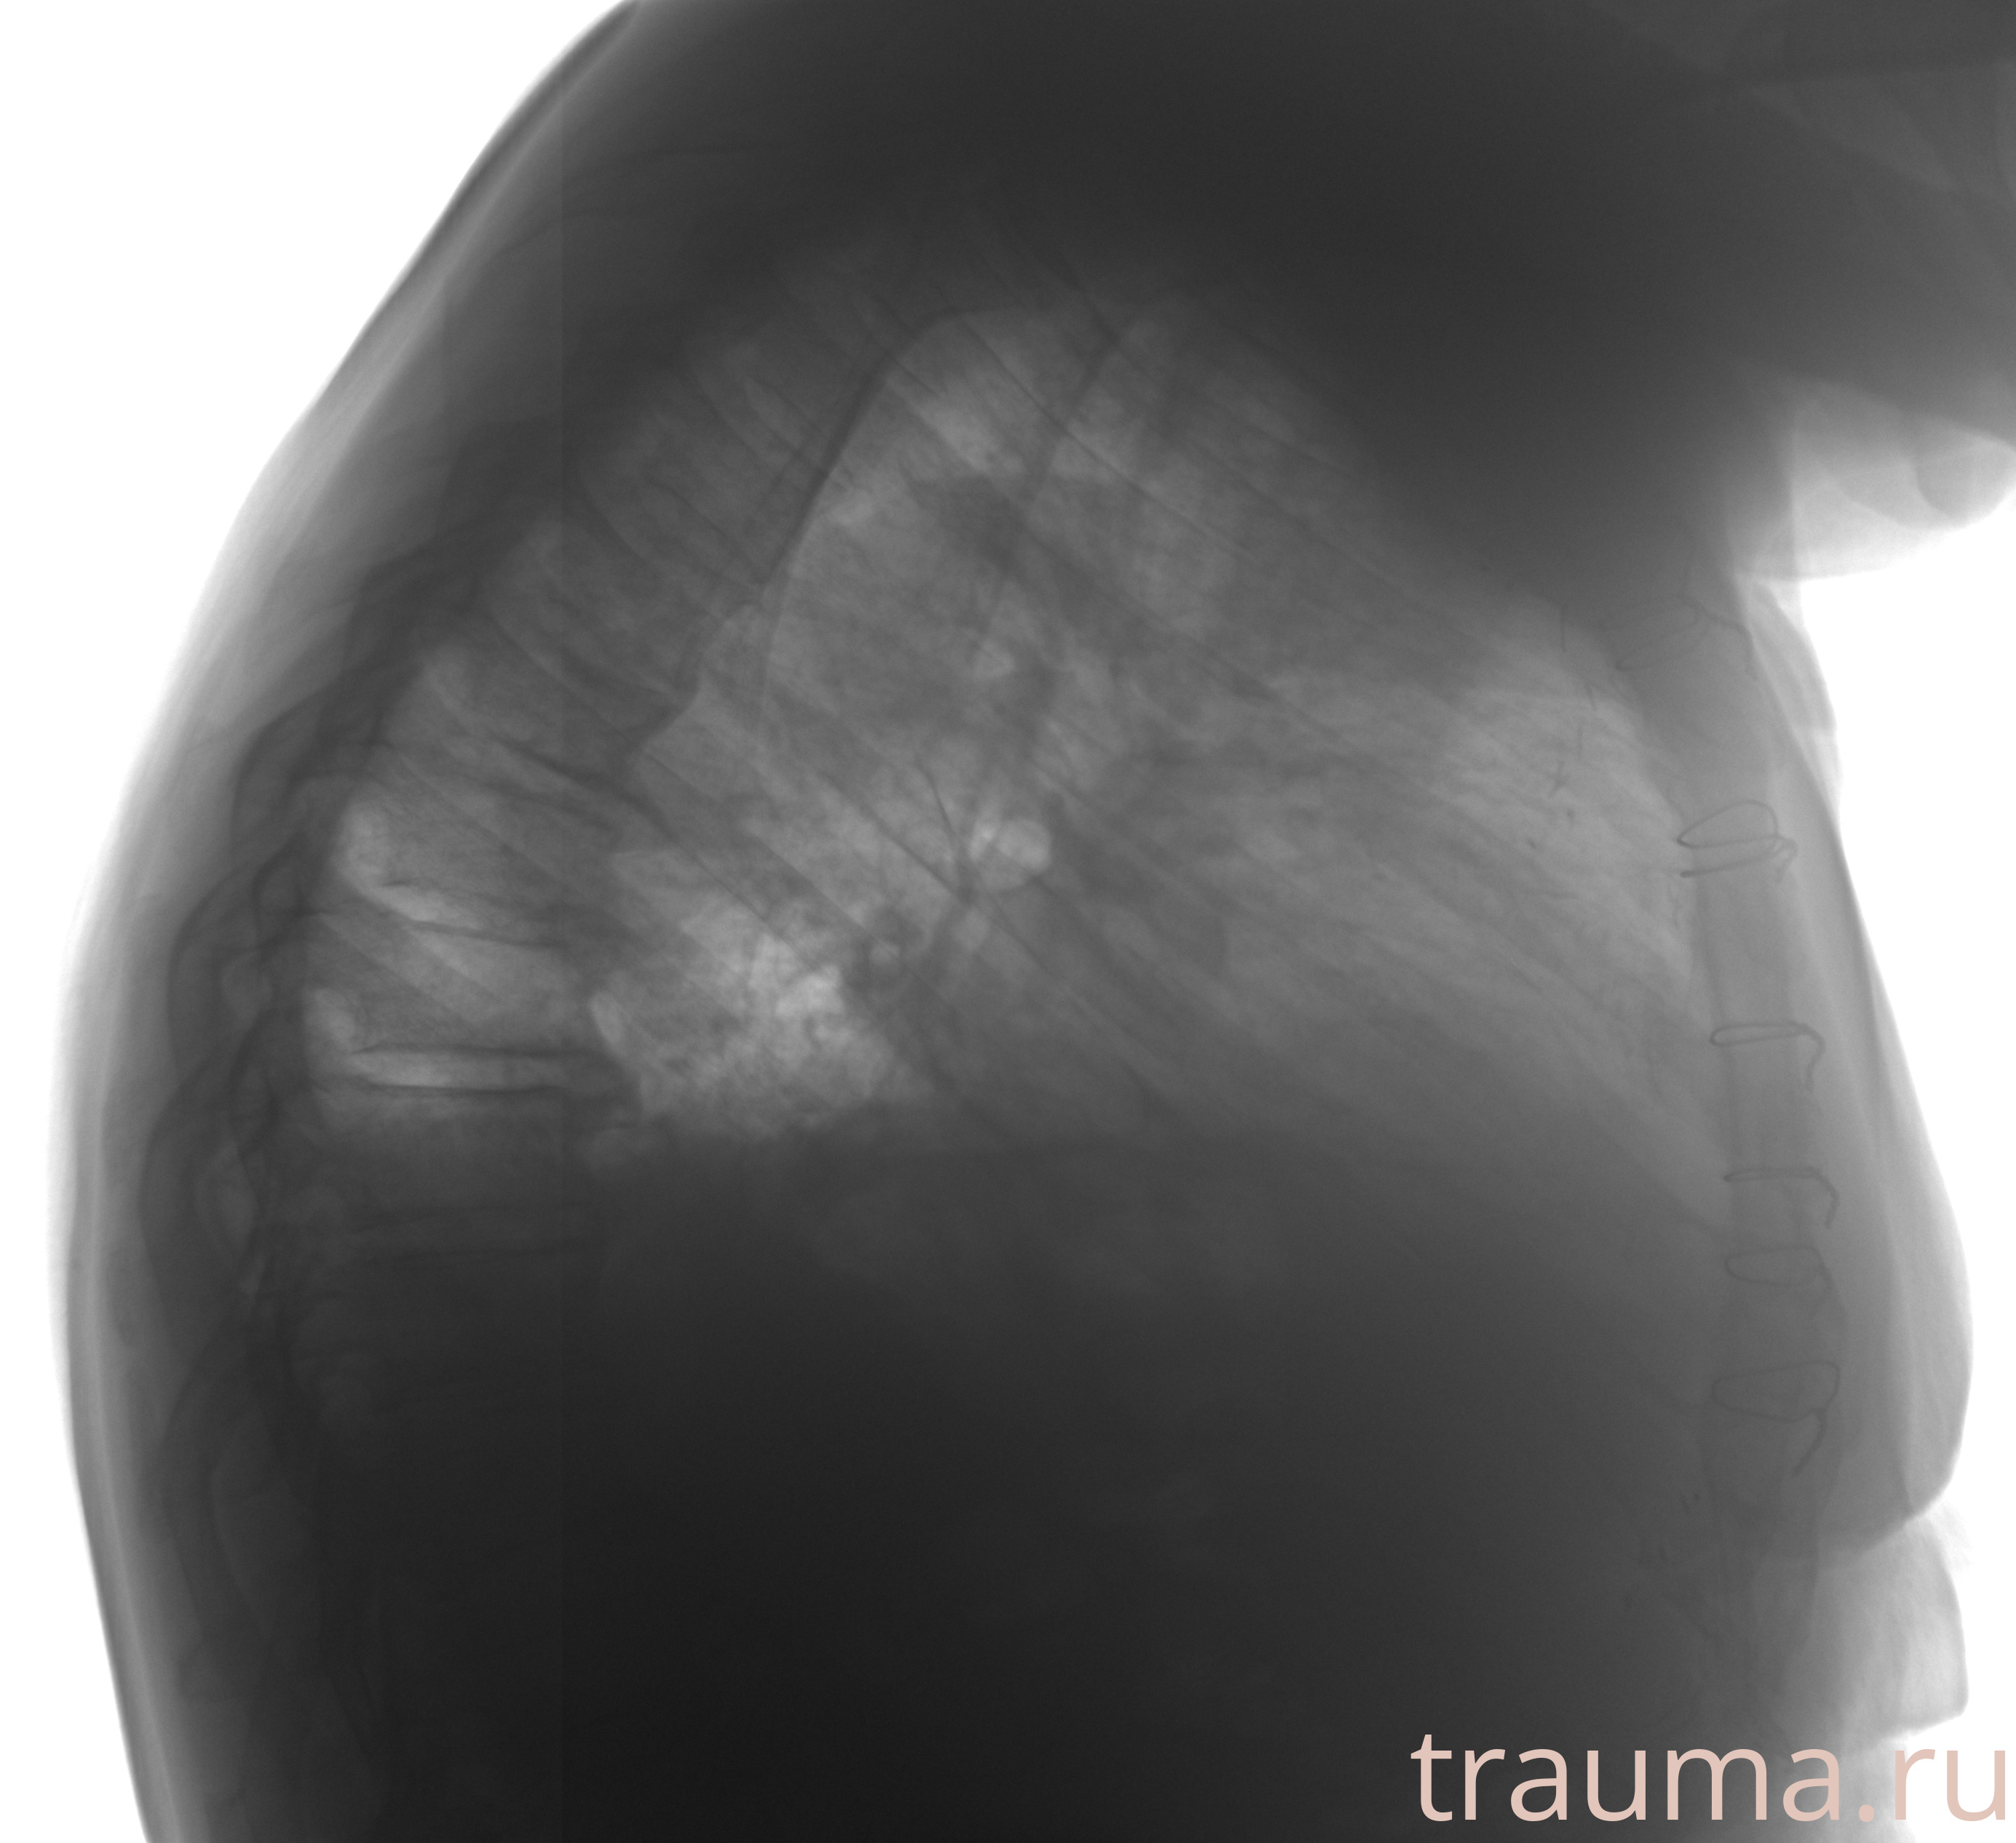

Рентгенограммы

Рентген на дому: по вашему адресу приезжает врач-рентгенолог, травматолог-ортопед с мобильным рентгеновским аппаратом, проводит диагностику травмы или заболевания, делает необходимые рентгенограммы, дает рекомендации по дальнейшему лечению. Получить качественные снимки в домашних условиях возможно благодаря уникальной методике, разработанной МосРентген Центром для института  Склифосовского